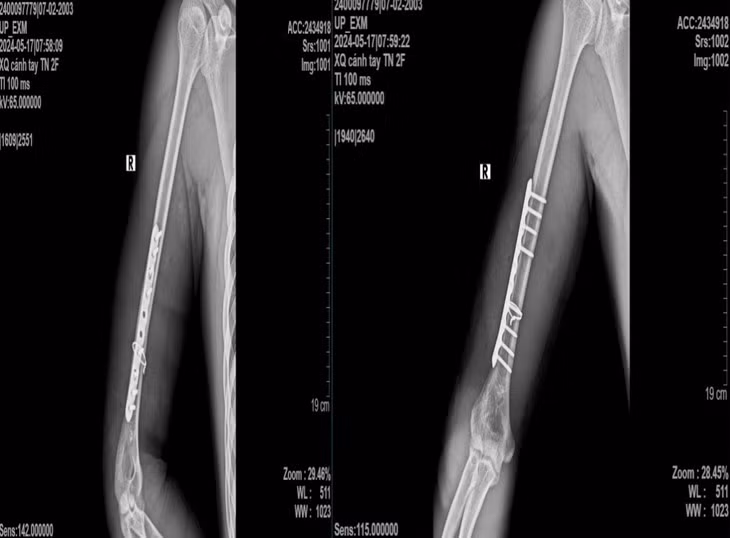

Sau phẫu thuật kết hợp xương nẹp vít, người bệnh được chụp x-quang kiểm tra sau mổ, giải phẫu xương cánh tay được phục hồi, người bệnh ra viện sau 4 ngày.

Người bệnh tái khám sau 1 tháng, vết mổ liền sẹo tốt, vận động cánh cẳng tay phải được, không tê bì yếu liệt đầu chi.

| Hình ảnh x-quang sau phẫu thuật của bệnh nhân - Ảnh: BVCC |